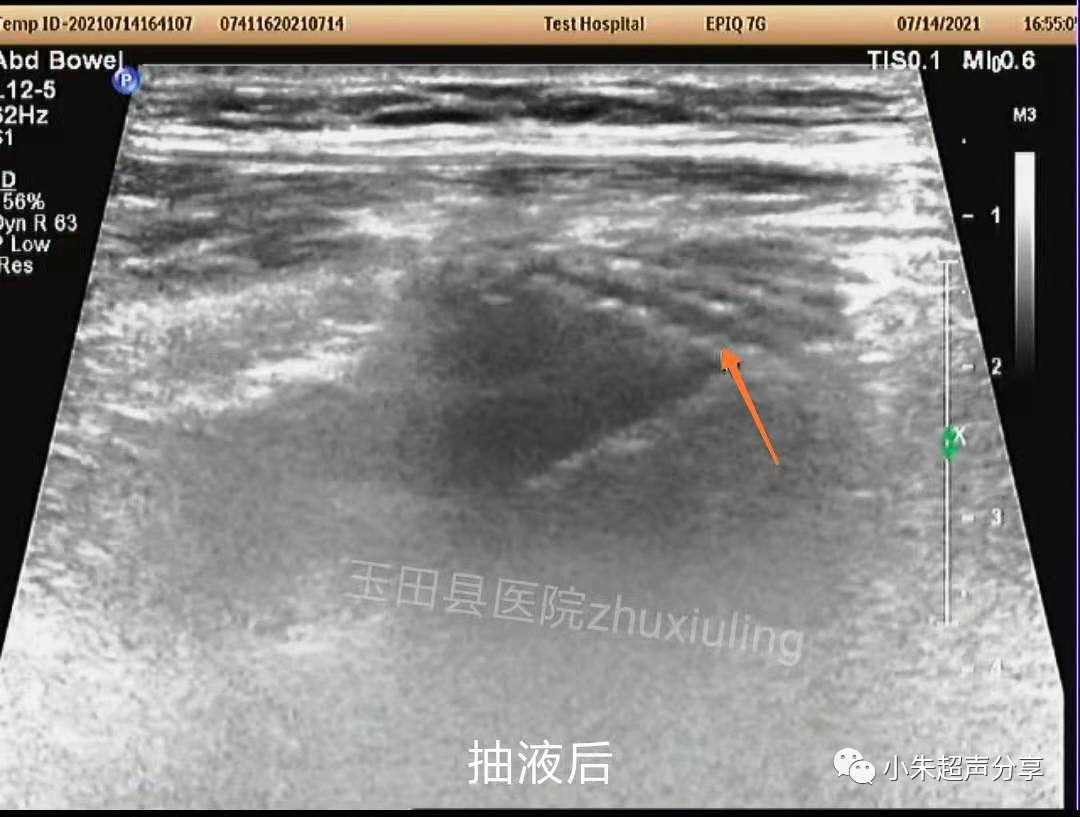

与临床医生沟通后,临床医生行超声引导下腹股沟区抽液。站立位,抽出淡红色液体约50ml。

抽液后,右下腹液体减少、消失。补片紧贴前腹壁。